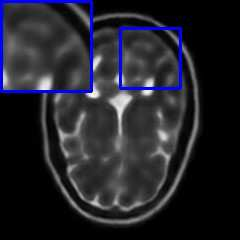

Limited by imaging systems, the reconstruction of Magnetic Resonance Imaging (MRI) images from partial measurement is essential to medical imaging research. Benefiting from the diverse and complementary information of multi-contrast MR images in different imaging modalities, multi-contrast Super-Resolution (SR) reconstruction is promising to yield SR images with higher quality. In the medical scenario, to fully visualize the lesion, radiologists are accustomed to zooming the MR images at arbitrary scales rather than using a fixed scale, as used by most MRI SR methods. In addition, existing multi-contrast MRI SR methods often require a fixed resolution for the reference image, which makes acquiring reference images difficult and imposes limitations on arbitrary scale SR tasks. To address these issues, we proposed an implicit neural representations based dual-arbitrary multi-contrast MRI super-resolution method, called Dual-ArbNet. First, we decouple the resolution of the target and reference images by a feature encoder, enabling the network to input target and reference images at arbitrary scales. Then, an implicit fusion decoder fuses the multi-contrast features and uses an Implicit Decoding Function~(IDF) to obtain the final MRI SR results. Furthermore, we introduce a curriculum learning strategy to train our network, which improves the generalization and performance of our Dual-ArbNet. Extensive experiments in two public MRI datasets demonstrate that our method outperforms state-of-the-art approaches under different scale factors and has great potential in clinical practice.